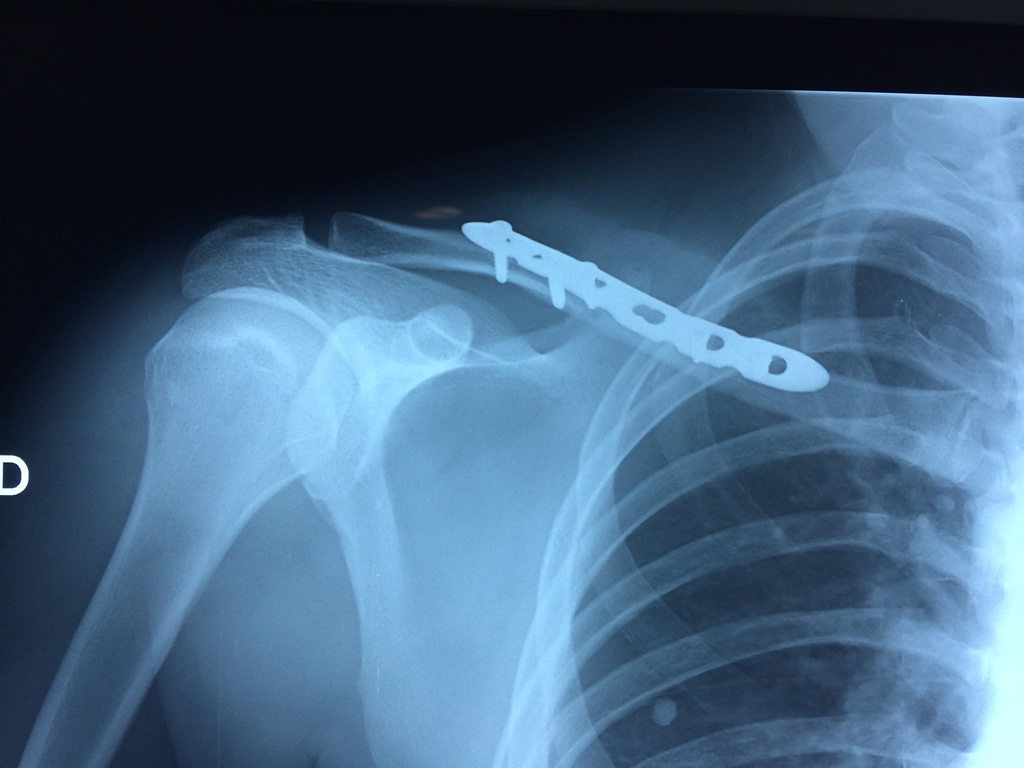

Cirugías de Codo - Clavícula

La clavícula es un hueso largo, con forma de "S" itálica, situado en la parte anterosuperior del tórax. Junto con la escápula forman la cintura escapular. Se puede palpar por toda su longitud y se extiende del esternón al acromion de la escápula, siguiendo una dirección oblicua lateral y posterior.